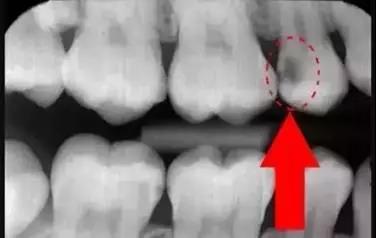

牙齒的牙根是埋在牙槽骨中的,醫(yī)生沒有透視眼,為了解患牙的牙根的形態(tài)、走向、長度及根尖周有無病變及病變大小,或者懷疑有肉眼無法確認(rèn)的其它牙科問題,都會建議患者去牙科的X光,甚至,口腔CT來全面性地確認(rèn)問題,以訂定合適的治療計(jì)劃。

牙片(牙科X光)有助于牙醫(yī)直接觀察到普通口腔檢查難以發(fā)現(xiàn)的牙齒和牙周組織問題,是早發(fā)現(xiàn)早治療口腔問題的關(guān)鍵。希望大家一定要認(rèn)識到牙片的重要性,拍片醫(yī)生不是為了訛?zāi)沐X,拍片沒有很大的風(fēng)險,大家不要擔(dān)心!